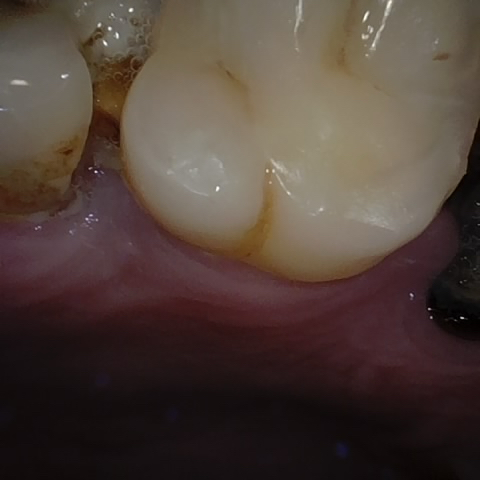

Annotated as "Good"